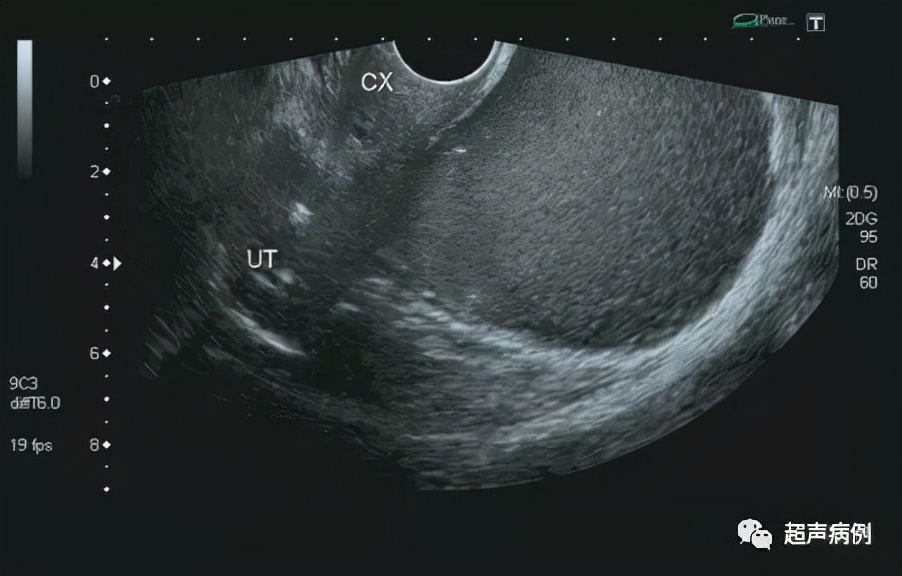

张珊(化名),女,62岁,因“左侧臀部疼痛1天,发现盆腔包块半天”入院。

超声检查:

前位子宫,形态、大小正常

在子宫后方盆腔内查见一约10.4x9.7x7.3cm无回声区

形态规则,边界清楚,内透声差,呈毛玻璃样改变

内可见强回声分隔

CDFI:该无回声区内部及周边未见明显血流信号。

双侧卵巢显示不清。